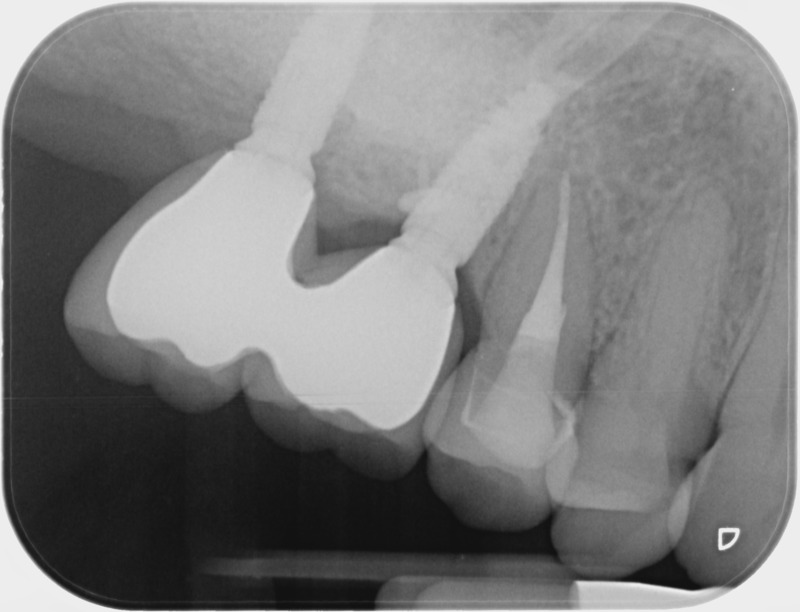

Après

• Reprise de traitement endodontique : La manœuvre consiste à retourner à l’intérieur des racines d’une dent déjà traitée. Il arrive occasionnellement qu’une nouvelle inflammation se déclare suite à une reprise de carie ou une fracture de la dent, ou si le premier traitement endodontique est incomplet. Après s’être assuré que la dent lésée était conservable, il convient de désinfecter de nouveau le réseau canalaire parfois très complexe. La nouvelle obturation des canaux devra être protégée aussi rapidement que possible pour éviter une éventuelle contamination bactérienne.